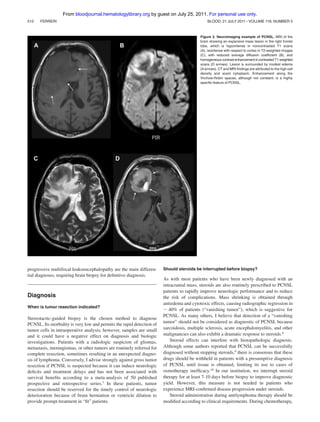

Figure 2. Neuroimaging example of PCNSL. MRI of the

brain showing an expansive mass lesion in the right frontal

lobe, which is hypointense in noncontrasted T1 scans

(A), isointense with respect to cortex in T2-weighted images

(C), with reduced average diffusion coefficient (B), and

homogeneous contrast enhancement in contrasted T1 weighted

scans (D arrows). Lesion is surrounded by modest edema

(A arrows). CT and MRI findings are attributed to the high cell

density and scant cytoplasm. Enhancement along the

Virchow-Robin spaces, although not constant, is a highly

specific feature of PCNSL.